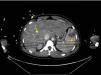

Gradually, the patient stabilized both from a respiratory and hemodynamic perspective, allowing for her transfer for further evaluation using computed tomography (CT), which revealed multiple pulmonary abscesses (Fig. 1), 2 liver abscesses, and splenic infarction (Fig. 2)1; no findings were noted in the brain.